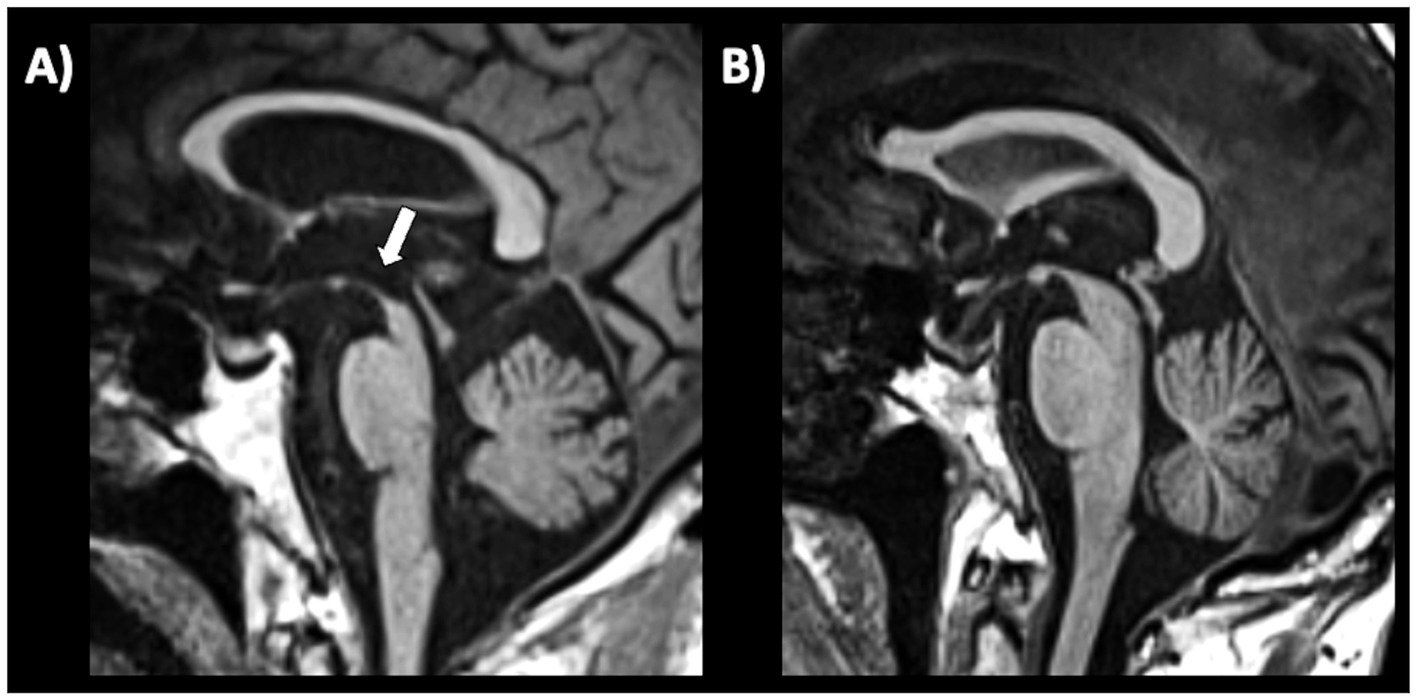

Several qualitative radiological signs have been identified for differentiation between PD and atypical parkinsonian disorders. The sensitivity and specificity of these MRI signs, however, are variable and depend on the disease stage, ranging from reasonably good performance in advanced stages to rather poor at the beginning of the disease. Some of the most recognized signs include the “hummingbird” sign (flat or concave midbrain tegmentum [beak] with preserved pontine volume [body] in the sagittal plane forming the silhouette of the head of a hummingbird or king penguin), shown in Figure 5 (184), the “morning glory flower” sign (reduced anteroposterior midbrain diameter with concavity of the lateral margin of the midbrain tegmentum in the axial plane resembling a lateral view of the morning glory flower) (185) and the “Mickey Mouse” sign characterized on axial views by reduction in anteroposterior diameter of the midbrain and thinning of the cerebral peduncles (186, 187) supporting a diagnosis of progressive supranuclear palsy (PSP). In a large cohort of 481 patients with neurodegenerative parkinsonism (85 PSP, 289 PD and 97 MSA) and 79 healthy controls, the hummingbird sign was found in 55.3% of PSP patients and in <1% of PD patients, MSA patients and healthy controls (specificity >99%) (188). The presence of morning glory flower sign yielded a similar high specificity but showed even lower sensitivity (37.7%) for a diagnosis of PSP compared with non-PSP parkinsonism (PD and MSA) (188). In addition, both signs showed sensitivity of 35.3% in early clinically unclassifiable parkinsonism (188). Very recently, some authors compared the accuracy of different qualitative MRI signs (hummingbird, Mickey mouse, and Morning-glory signs) in differentiating PSP-Richardson’s syndrome (PSP-RS) and other PSP variants from healthy controls, showing that all these MRI signs had significantly better performances in identifying PSP-RS cases than PSP variants (189).

Figure 5

A 3T brain T1-weighted midsagittal MR image showing midbrain atrophy with hummingbird sign in a patient with progressive supranuclear palsy (A) and the normal midbrain appearance in a patient with Parkinson’s disease (B). A concave midbrain tegmentum is visible in the image on the left, forming the “beak” of the hummingbird.